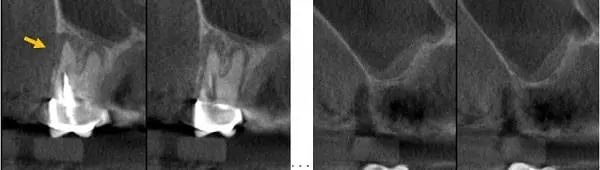

斷層顯示第一小臼齒外側骨頭已破洞 → 大臼齒區已經沒有骨頭,像蛋殼一樣薄

首先拔除左上第一小臼齒,做翻瓣不開側窗,然後在第五及第六顆缺牙處的骨頭,鑽兩個小洞(直徑3.2 mm),之後用手術器械墊高鼻竇,填入大量人工骨粉和再生膜,最後縫合就完成了。等待六個月後,就能植牙。

使用手術器械套組,安全墊高鼻竇 → 填入大量人工骨粉,外層覆蓋再生膜